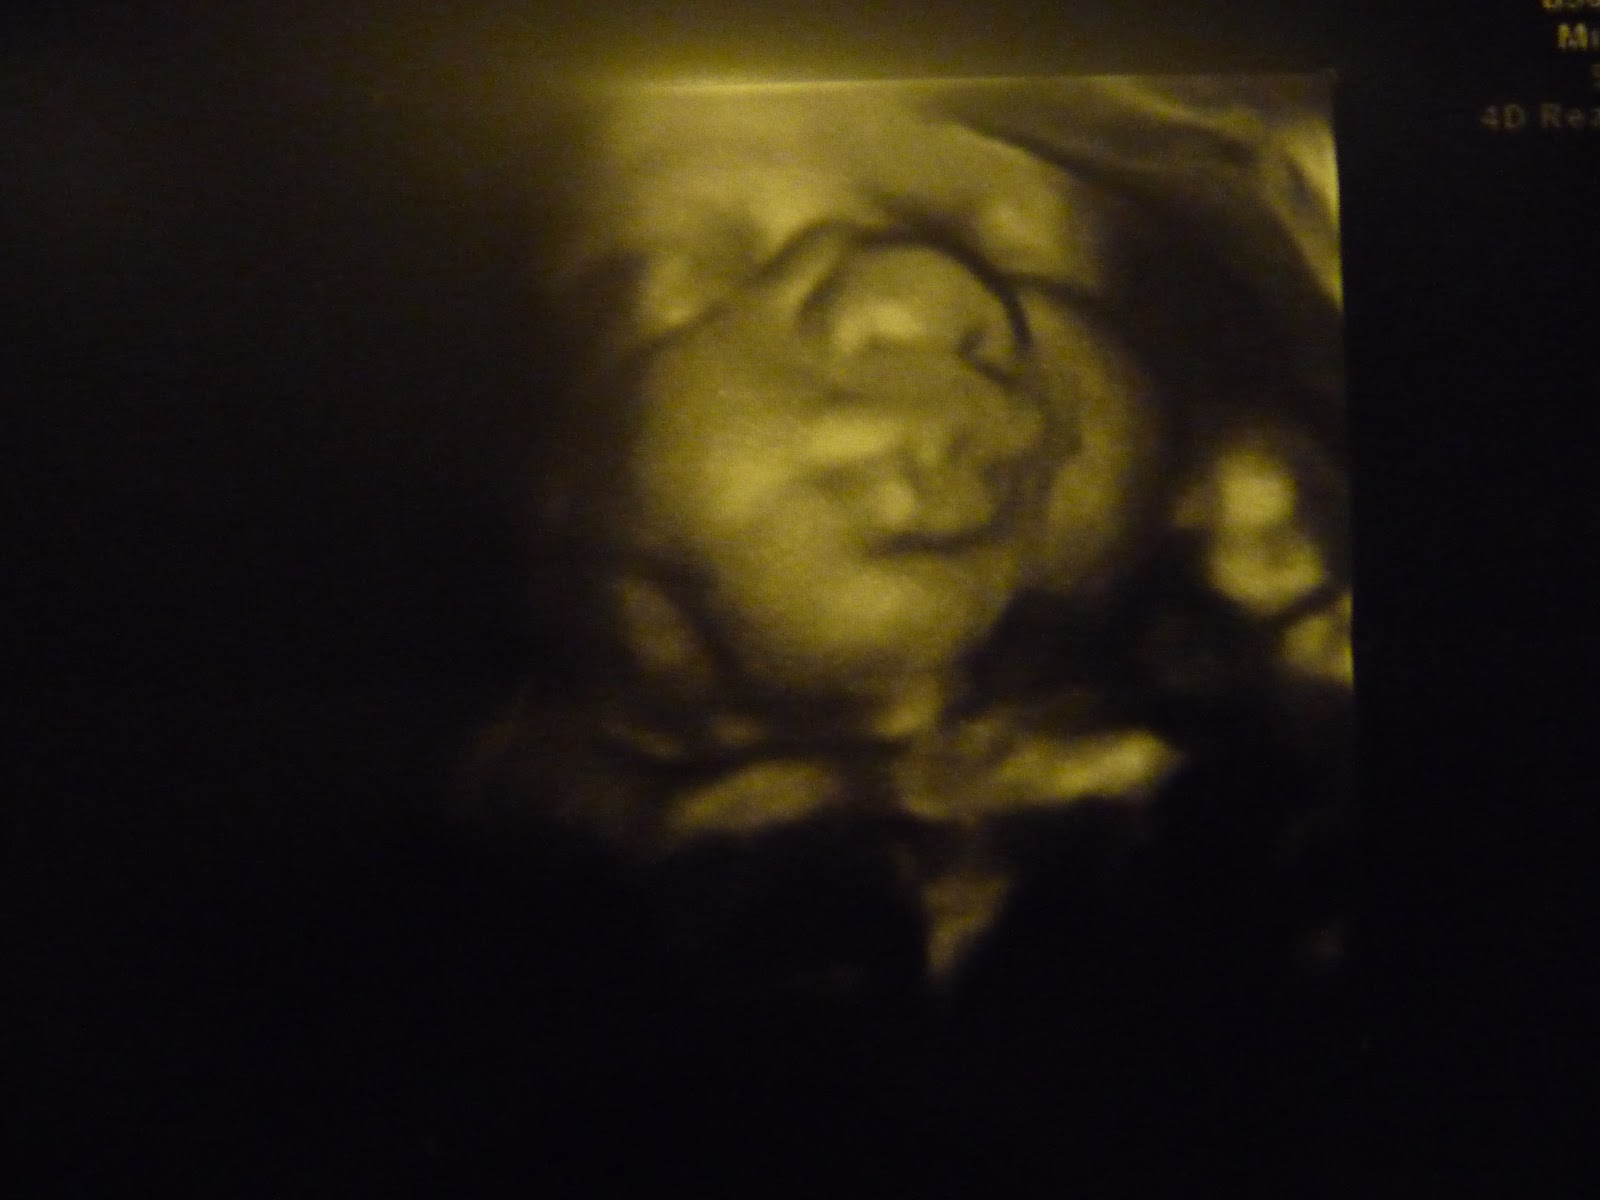

Kochani jak tam u Was po świętach?? Ja odpoczywam, niby powinny być spokojne, ale wtedy najwięcej roboty i jeżdżenia ;) także teraz odpoczywamy :) Dziś byłam na wizycie w lekarza. Maleństwo waży już 2200 g! A jaka z niego bułeczka!! Całkiem inny niż Adaś... Już po zdjęciach widzę. Będzie duży... jak do terminu donoszę to ze 4 kg jak nic...! Także zobaczymy jak będzie. Ale wiecie, cudne zdjęcie mamy z USG... najpierw dziubeczkiem robił jak rybka a potem posłał nam takiego całusa...... no sami zobaczcie!

Ale usteczka hi hi hi hi. Przeurocze to zdjęcie!! Napatrzeć się nie umiem!!